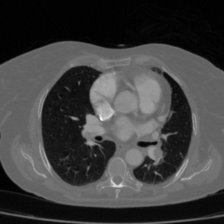

Pulmonary Embolism Detection (FUMPE Dataset): The FUMPE dataset (Ferdowsi University of Mashhad’s Pulmonary Embolism dataset) [21] contains the three-dimensional computed tomography angiography (CTA) scans of 35 patients, amounting to 8792 image slices. Two radiologists manually reviewed all the CTA scans using a semi-automated segmentation method to derive reference labels. In total, the dataset consists of 3,438 PE (pulmonary embolism) annotated regions. Notably, approximately 67% of these regions occur in the peripheral pulmonary arteries, which positions this dataset to be highly advantageous for prototyping and benchmarking sophisticated CAD systems. After a comprehensive review, we completed the collection of CTPA images for 35 patients, totaling 8792 CTPA images, along with updated annotations by the doctors. For performance evaluation, the dataset was divided into an ratio for training and validation. And performance metric were reported on unseen validation samples as suggested in [15].

Table 2 presents a quantitative comparison between the proposed DAUNet and several representative state-of-the-art segmentation models, including CNN-based, transformer-based, and hybrid architectures. The comparison is conducted on the FUMPE dataset using Dice Similarity Coefficient (DSC) and 95th percentile Hausdorff Distance (HD95), together with model parameter count as a measure of computational efficiency.

As shown in Table 2, the proposed DAUNet achieves the best overall segmentation performance, attaining a Dice score of 88.80% and the lowest boundary error with an HD95 of 2.57. These results indicate superior overlap accuracy and more precise boundary delineation compared to all competing methods. In addition, DAUNet maintains a significantly lower model complexity, requiring only 21.07M parameters, which is substantially fewer than several strong baselines.

Notably, models with considerably higher parameter counts, such as SCUNet++ (60.11M), do not achieve comparable segmentation accuracy or boundary robustness on this dataset. Transformer-based and hybrid models, including TransAttUNet and FAT-Net, demonstrate improved performance over classical UNet variants; however, they remain inferior to DAUNet in both DSC and HD95, while requiring higher computational cost.

Overall, these results highlight the effectiveness of the proposed lightweight architecture for pulmonary embolism segmentation. DAUNet consistently delivers superior accuracy and robustness while maintaining a compact model size, making it well suited for deployment in real-time and resource-constrained clinical environments.

Figure 4 and Figure 5 provide visual comparisons of segmentation masks generated by DAUNet and other competing methods on representative samples from both datasets. As illustrated in Figure 4, DAUNet produces more accurate and smoother boundary delineations, closely aligning with the ground truth annotations, even in challenging low-contrast regions or under partial occlusion. A similar performance can be observed in Figure 5, where proposed model accurately identify the pulmonary embolism regions. It is worth nothing that the proposed model achieve best performance in two different imaging modalities, consisting of different sized regions of interest and number of classes demonstrating a good generalization.